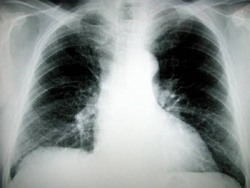

Αθήνα: Αμερικανοί ερευνητές, χρησιμοποιώντας γενετικές τεχνικές, ανακάλυψαν μια μέθοδο να εντοπίζουν εκείνους τους καπνιστές, που αντιμετωπίζουν τον μεγαλύτερο κίνδυνο να εμφανίσουν καρκίνο των πνευμόνων.